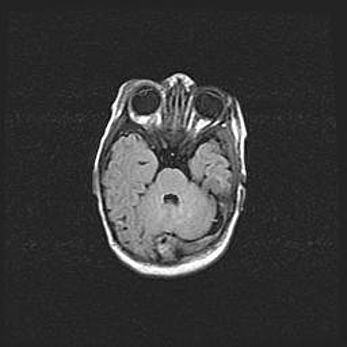

Множественные кисты обоих полушарий головного мозга, наибольшая из них в правой затылочной области. Ассиметричная атрофическая гидроцефалия.

Возраст: 7 месяцев

Вес: 5660 г

Пол: мужской

Окружность головы: 41,5 см

Срок гестации: 28-29 недель

Кисты головного мозга развиваются в результате многоочаговых некрозов вещества мозга и возникают вследствие перенесенной перинатальной инфекции, менингитов, энцефалитов, асфиксии, родовой травмы, расстройств мозгового кровообращения различного генеза. Образованию кист в веществе головного мозга плодов и новорожденных способствуют такие факторы, как высокое содержание в нем воды, недостаточная (или отсутствие) миелинизация и слабая астроглиальная реакция на повреждение.

Кисты могут сочетаться с гидроцефалией и другими поражениями головного мозга.